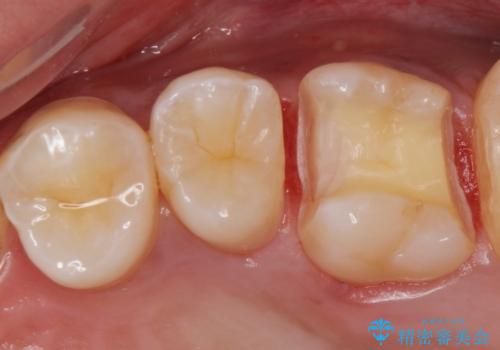

コンタクトカリエス治療。

- 歯と歯の間に虫歯(コンタクトカリエス)が見られたので拡大鏡下で取り除き、e-maxインレーで治療を行いました。